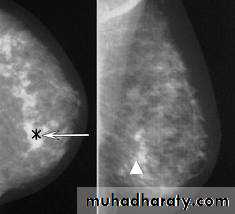

Most instances of breast cancer (mammary carcinomas) arise from epithelial cells of the lactiferous ducts.

Cell spreading (or metastasizing) from the carcinoma via the circulatory or lymphatic vessels to critical organs such as the lungs or brain are responsible for the mortality associated with breast cancer.

Axillary lymph nodes are removed surgically and examined histologically for the presence of metastatic mammary carcinoma cells.

MEDICAL APPLICATION

Early detection through

self-examinationMammography

ultrasound

and consequent early treatment have significantly reduced the mortality rate